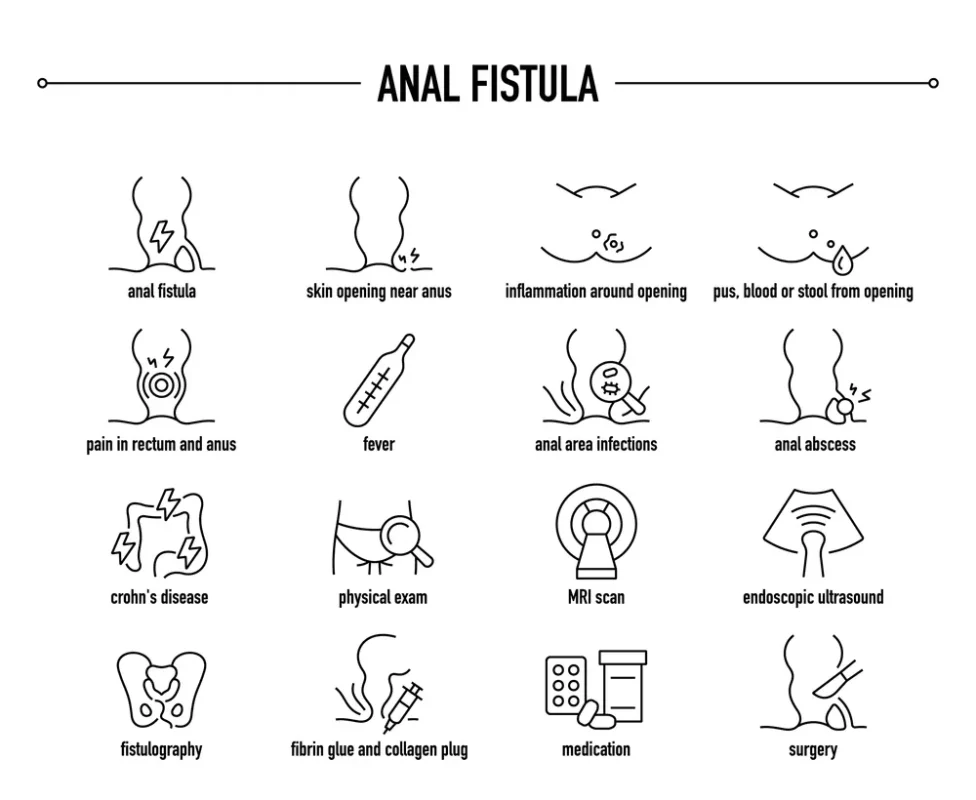

فیستول مقعدی و مسیر غیرطبیعی بین روده و پوست

فیستول مقعدی یک کانال غیرطبیعی بین دیواره روده و پوست اطراف مقعد است که معمولاً در اثر عفونتهای مزمن یا آبسههای درمان نشده ایجاد میشود. این وضعیت منجر به ترشح مداوم چرک، درد، تورم و التهاب موضعی می شود و کیفیت زندگی فرد را به شدت تحت تأثیر قرار می دهد.

علل ایجاد فیستول مقعدی

آبسه مقعدی درمان نشده: شایعترین عامل فیستول، گسترش عفونت از آبسههای قبلی است.

بیماریهای التهابی روده: کرون و دیگر بیماریهای التهابی باعث التهاب مزمن و ایجاد مسیر غیرطبیعی بین روده و پوست می شوند.

ضربه یا جراحی ناحیه مقعد: آسیب مستقیم یا عمل جراحی قبلی گاهی زمینهساز تشکیل فیستول میشود.

علائم فیستول مقعدی

- ترشح مداوم یا گاهبهگاه چرک و خون از دهانه فیستول

- درد و حساسیت در ناحیه مقعد و اطراف آن

- تورم و قرمزی پوست در مسیر کانال فیستول

- بوی ناخوشایند ترشحات در برخی موارد

اهمیت درمان به موقع

درمان فیستول مقعدی نیازمند مداخله تخصصی جراحی است، زیرا درمانهای غیرجراحی معمولاً موفقیت محدودی دارند و عود بیماری رایج است. روشهای درمان شامل فیستولوتومی، لیزر درمانی و در موارد پیچیده استفاده از پلاگ یا استنت فیستول است. درمان سریع مانع از تشکیل عفونتهای ثانویه، آبسه مجدد و آسیب بافتی گسترده میشود.